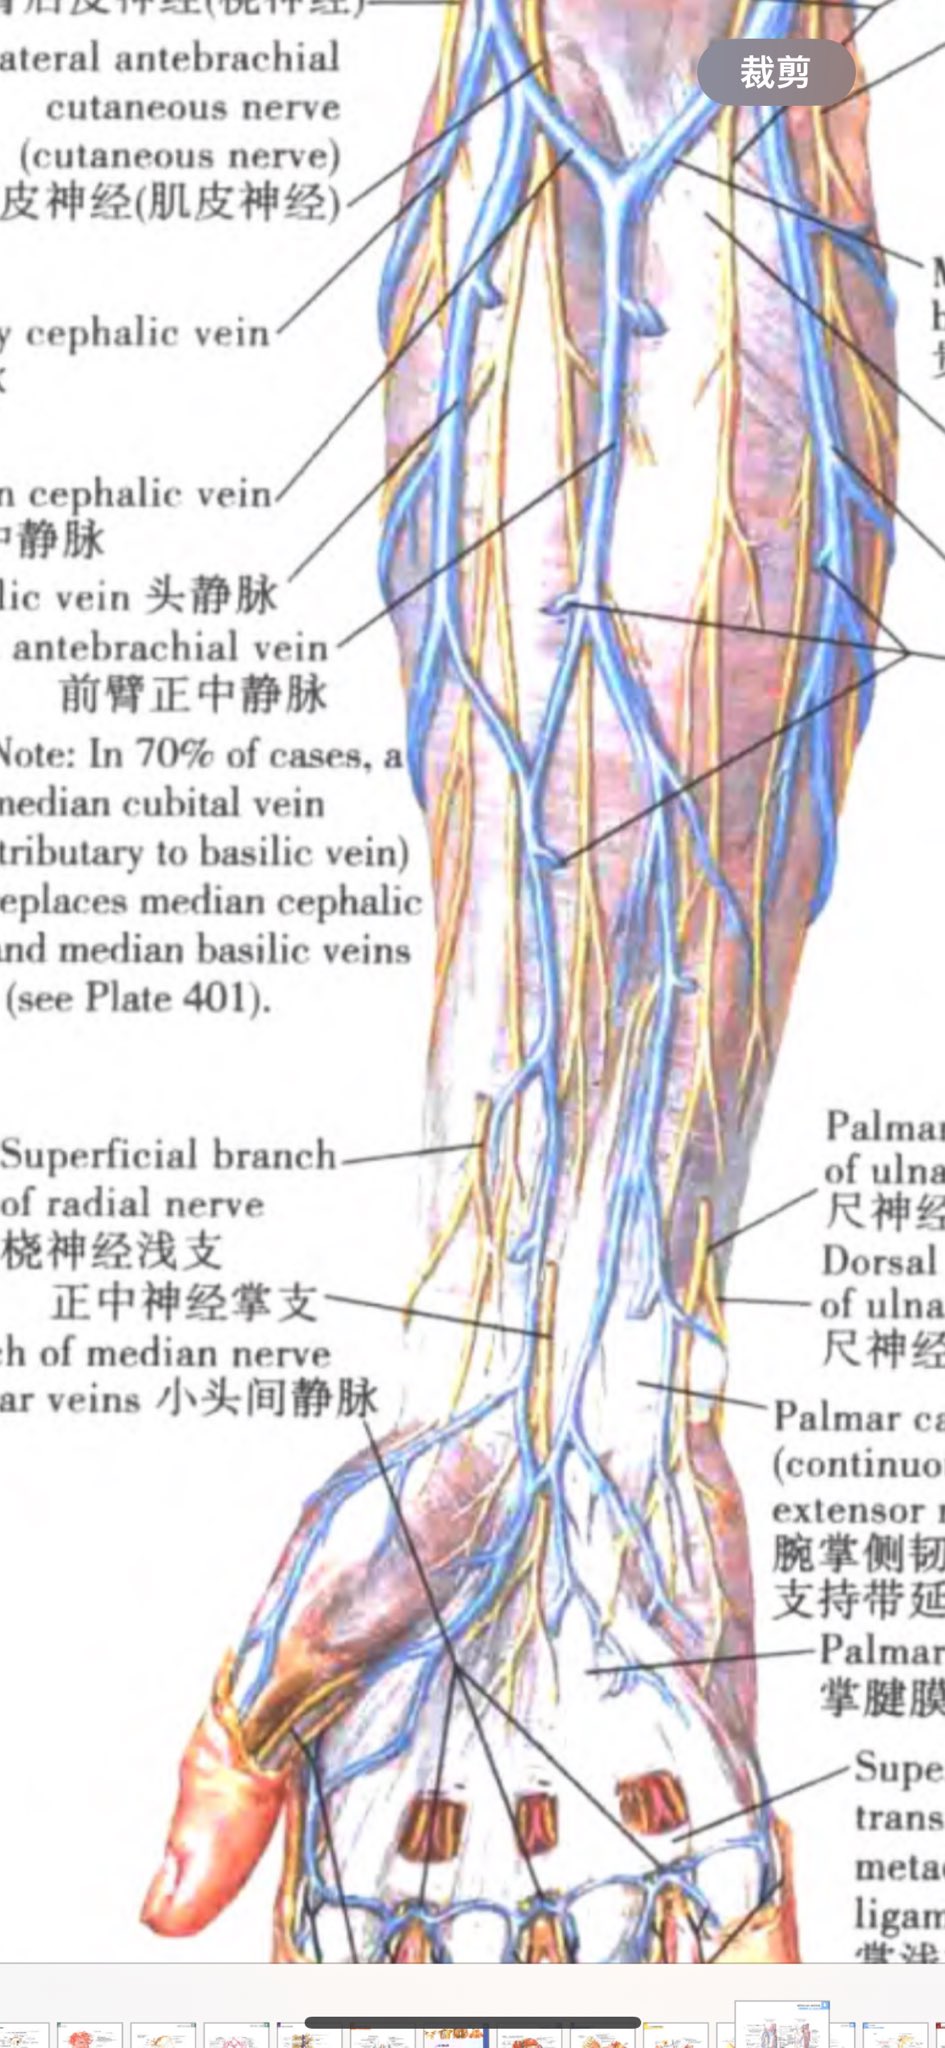

2026-03-04 19:15:41 UTC

果然蝴蝶针会翻车,太难用了。

*我竟然无师自通留置针了!用的肘静脉因为其他地方被蝴蝶针霍霍了

配合另一种麻醉就可以无痛重开了(bushi) https://t.co/Uj139Q2tBk

炽烈已极 @AnIncandescence@Cheese_Ghostfox @Meeeauw_ 哇对哎可以用弹力绷带……但是缠完怎么单手扯断啊..!感觉一整个单手都挺难操作的。

☯️🧬霊狐製作所 公式ツイッター @Cheese_Ghostfox@AnIncandescence 对于自我静脉注射来说,Y形留置针是最好的选择

毕竟单手退钢针和单手扶针+贴输液贴同时还要保持被扎的那只手不动的难度压根不是一个数量级的🤔

炽烈已极 @AnIncandescence@Cheese_Ghostfox 不过药量小并且确认单次给药的我会注射器直推(问就是省事)反正现在在医院我是没见过这种操作

炽烈已极 @AnIncandescence@Cheese_Ghostfox 嗯?其实角度贴近平行血管的话其实还好,移动一下都没问题,大概是维持了进针的角度才会穿吧()

但是蝴蝶针那个乱转是真的绷不住,像条鱼一样。。啊不蝴蝶?现在知道为什么叫蝴蝶针了x